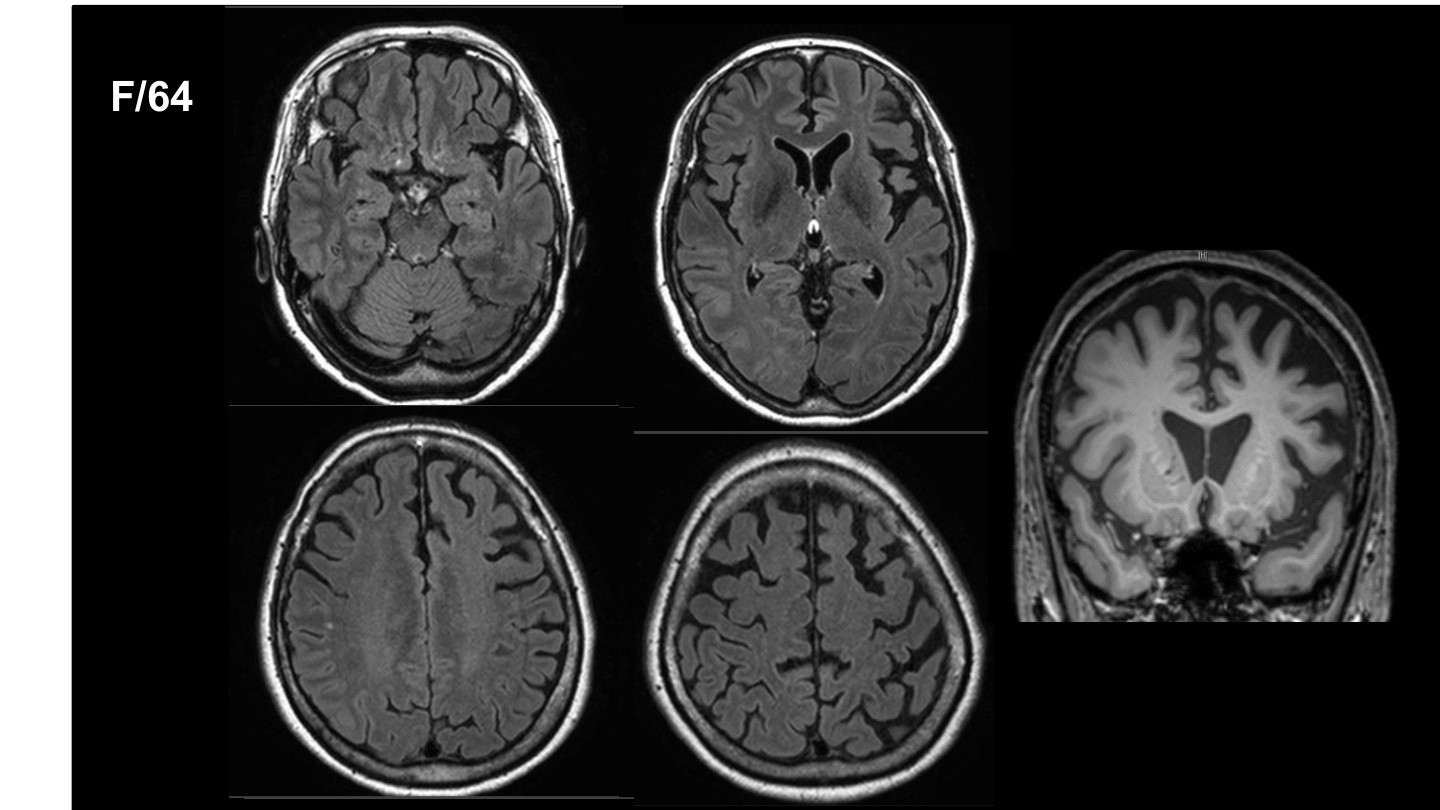

현재 삼성서울병원 신경과 교수로 재직 중이신 김준표 교수님은 신경과 레지던트, 전임의, 임상조교수로 활동하시며 대한치매학회 위원으로서 치매와 신경과학 분야에서 깊은 전문성과 풍부한 경력을 쌓아오셨습니다. 특히, SCI급 논문 55편을 게재하며 학문적 연구에도 크게 기여하셨습니다. 이번 강연에서는 치매의 진단, 치료, 예방에 대한 귀중한 통찰을 나눠주실 예정입니다.

현대사회에서 치매는 우리 주변에서 점점 더 빈번하게 접할 수 있는 중요한 건강 문제로 떠오르고 있습니다. 이번 강의를 통해 치매를 진단하고, 효과적으로 치료하며, 예방할 수 있는 실질적인 방안에 대해 알아볼 수 있는 소중한 시간을 가질 수 있을 것 같습니다. 치매 분야에서 오랜 경험을 지닌 교수님의 강의를 통해 치매에 대한 더 깊은 이해와 대비책을 마련할 기회를 함께 가져보시길 바랍니다.